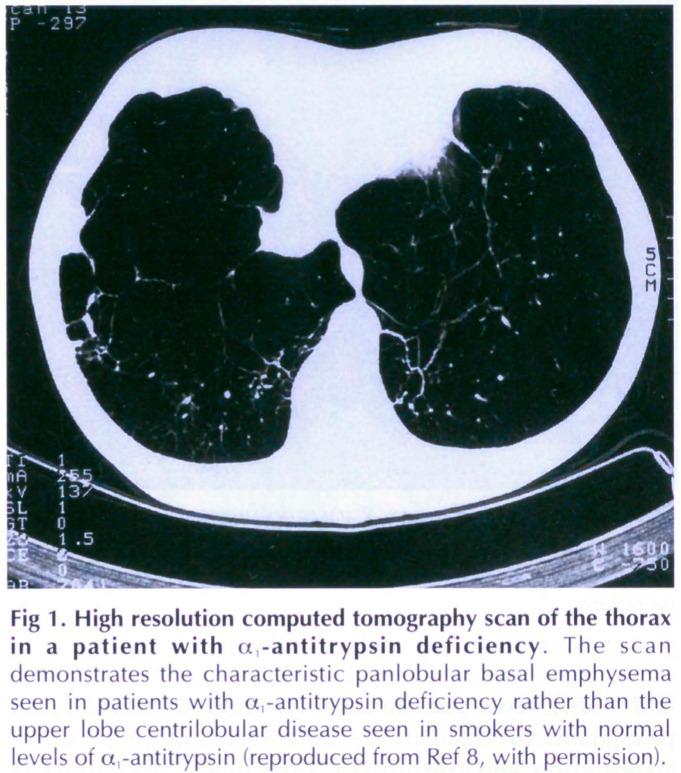

Alpha-1-antitrypsin deficiency results from point mutations that distort the structure of the protein to allow a unique protein-protein interaction that we have termed loopsheet polymerisation. Polymers of Z alpha 1-antitrypsin accumulate within hepatocytes to form inclusion bodies that are associated with juvenile cirrhosis and hepatocellular carcinoma. The lack of circulating protein predisposes the Z alpha 1-antitrypsin homozygote to emphysema. This process also occurs in other members of the serine proteinase inhibitor (serpin) superfamily, antithrombin, C1-inhibitor and alpha 1-antichymotrypsin, in association with thrombosis, angioedema and chronic obstructive pulmonary disease, respectively, and we have recently shown that it underlies a novel inclusion body dementia. The interaction provides a useful paradigm for other 'conformational diseases' such as Huntington's disease, Creutzfeldt-Jakob disease and the amyloidoses.

α-1-抗胰蛋白酶缺乏症是由点突变引起的,这些突变会扭曲蛋白质的结构,从而产生一种独特的蛋白质-蛋白质相互作用,我们将其称为环片聚合。Z型α-1-抗胰蛋白酶的聚合物在肝细胞内积累,形成与青少年肝硬化和肝细胞癌相关的包涵体。循环蛋白的缺乏使Z型α-1-抗胰蛋白酶纯合子易患肺气肿。这个过程也发生在丝氨酸蛋白酶抑制剂(serpin)超家族的其他成员中,抗凝血酶、C1抑制剂和α-1-抗糜蛋白酶,分别与血栓形成、血管性水肿和慢性阻塞性肺疾病有关,并且我们最近发现它是一种新型包涵体痴呆的基础。这种相互作用为其他“构象性疾病”,如亨廷顿舞蹈症、克雅氏病和淀粉样变性病,提供了一个有用的范例。